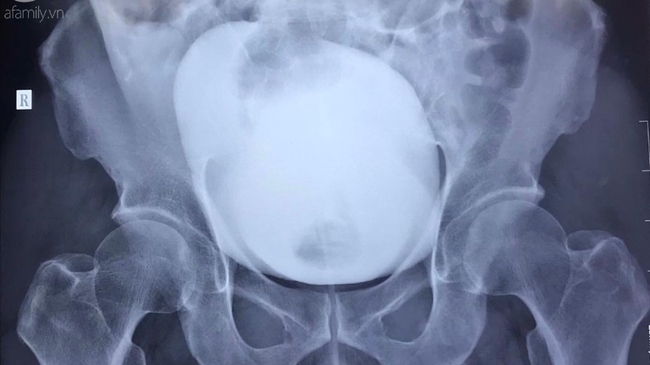

Nhịn tiểu từ Vũng Tàu về TP.HCM, người đàn ông trượt chân té vỡ bàng quang

Sau khi di chuyển từ tiệc cưới tận Vũng Tàu về TP.HCM, người đàn ông vào nhà vệ sinh để tiểu tiện thì trượt chân té vỡ bàng quang.